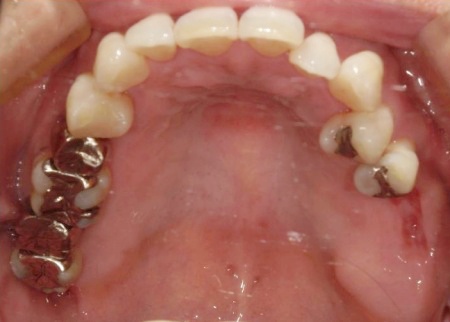

また、右下奥歯には、両隣の歯を土台にして橋を渡すように欠損部を補う被せ物「ブリッジ」が装着されていました。

右下奥歯は2本欠損しており、親知らず(第3大臼歯)と手前の奥歯(第2小臼歯)の2本でブリッジを支えていますが、これは親知らずに過度な負荷がかかる構造です。

親知らずはすでに大きく傾いており、こちらも温存が難しいため、ブリッジを除去してから親知らずを抜く必要があります。

以上のことから、ブリッジの除去と併せて、温存が難しい左上奥歯2本と右下の親知らず1本を抜き、欠損部位を補う治療を検討する必要があると診断しました。